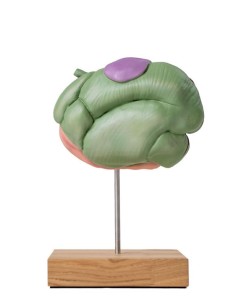

- Chien : nous proposons une sélection de simulateurs pour chiens, idéaux pour pratiquer un large éventail de procédures diagnostiques et thérapeutiques sur cette espèce animale commune.

- Chat : les simulateurs pour chats permettent de s'entraîner aux procédures vétérinaires spécifiques à cette espèce, offrant ainsi une formation complète et précise aux professionnels.

- Cheval : pour les professionnels travaillant avec des équidés, nous proposons des simulateurs précis et réalistes pour pratiquer des procédures diagnostiques, thérapeutiques et chirurgicales sur les chevaux.

- Souris : les simulateurs de souris sont essentiels pour la formation pratique à la recherche biomédicale et aux soins des animaux de laboratoire, car ils offrent une formation complète et compétente au personnel vétérinaire.

- Vache : pour ceux qui travaillent avec des animaux de ferme, nous proposons des simulateurs de vache pour pratiquer des procédures diagnostiques et thérapeutiques spécifiques à l'espèce.

Chaque catégorie propose une sélection de simulateurs de haute qualité, fabriqués à partir de matériaux durables et réalistes, afin de garantir une expérience de formation pratique efficace et précise.

Les simulateurs vétérinaires offrent une occasion unique d'acquérir une expérience pratique des soins et du traitement des animaux domestiques et de ferme. En ayant accès à une large gamme de simulateurs précis et réalistes, les professionnels vétérinaires peuvent améliorer leurs compétences en matière de diagnostic, de thérapie et de chirurgie, garantissant ainsi des soins sûrs et efficaces aux animaux. Investissez dans votre formation vétérinaire et préparez-vous à relever les défis de la pratique vétérinaire avec confiance et compétence.